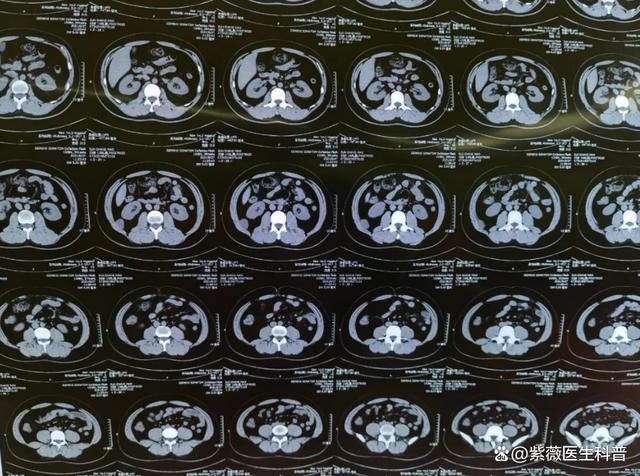

2、核磁共振检查核磁共振检查利用磁场和射频波对人体进行成像,对于软组织成像尤为清晰MRI检查常用于检查脑部脊柱关节等部位的肿瘤,以及评估肿瘤对周围组织的侵犯情况病理学检查病理学检查是癌症诊断的金标准通过取样获取病变组织或细胞,然后经过一系列处理后进行显微镜观察,以确定是否存在癌细胞及其;癌症筛查中,CT核磁共振和四维PETCT检查的主要区别及准确性分析如下1 检查原理与侧重点不同 CT主要通过X射线对人体进行断层扫描,着重于显示体内组织器官的结构变化当器官出现形态上的改变,如肿瘤增大导致的占位性病变时,CT能够清晰地捕捉到这些变化 核磁共振利用磁场和射频波来生成体内组织;做磁共振检查能查出癌症,磁共振检查是临床用于检查癌症常用的影像学手段之一通过磁共振检查可以很好的找出癌症所在,做到准确的定位磁共振检查主要应用于软组织,以及神经组织中癌症的查找,例如如果患者出现剧烈头痛,不能缓解,可以做头颅磁共振,通过头颅磁共振可以及时发现颅内占位性病变通过做增强检查,可以进一步判断颅内占位性病变是良性还是恶性,以及它的累及范围;综合诊断的重要性在实际诊断过程中,医生通常会结合患者的病史临床表现其他影像学检查和实验室检查等多方面的信息来综合判断,以提高诊断的准确性因此,虽然核磁共振在癌症诊断中具有重要的价值,但并不能单凭核磁共振就确诊癌症需要综合考虑多种检查手段和信息来做出最终的诊断。

3、癌细胞检查的指标主要包括以下几项血液学指标肿瘤标志物如癌胚抗原,主要用于检测结肠癌CA199,在胰腺恶性肿瘤中可能会显著升高甲胎蛋白,在肝癌中可能会明显升高影像学指标CT通过计算机断层扫描技术,可以发现体内的占位性病变,是检查癌症病灶的重要手段核磁共振能够提供更详细的软组织;癌症的检查主要通过以下几种方法影像学检查彩超检查适用于初步筛查某些器官是否存在肿块CT检查通过X射线计算机断层扫描,可以清晰地显示人体某个断面的组织密度分布,对多种癌症具有较高的诊断价值核磁共振检查利用磁场和射频波生成详细的体内结构图像,对软组织分辨率较高,适用于神经系统肌肉;确保诊断的准确性明确癌灶范围核磁共振可以显示宫颈的全部组织,并观察宫颈下段受侵的具体程度,有助于医生了解癌灶的大小位置和浸润深度,为制定治疗方案提供依据特别是对于包块较大的宫颈癌患者,核磁共振可以明确癌灶范围,避免误诊为早期癌症而进行不恰当的处理。